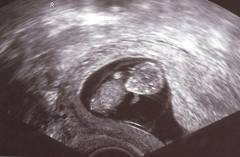

Heute stellen wir uns wir uns einem heiklen Thema. Im Strafrecht, §97 ist das Abtreibungsrecht geregelt. Bis zum dritten Monat ist die Abtreibung straffrei. Wenn aber festgestellt wird, dass der Fötus »geschädigt« ist und das neugeborene Kind mit einer Behinderung zur Welt kommen könnte, ist die Abtreibung bis vor der Geburt möglich.

Wir haben den Titel für die heutige Sendung gewählt »Die Guten ins Töpfchen, die Schlechten ins Kröpfchen«, dieser Passus, der im Abtreibungsrecht als »Eugenische Indikation« bezeichnet wird, wurde und wird von der Interessensvertretung der behinderten Menschen kritisiert.